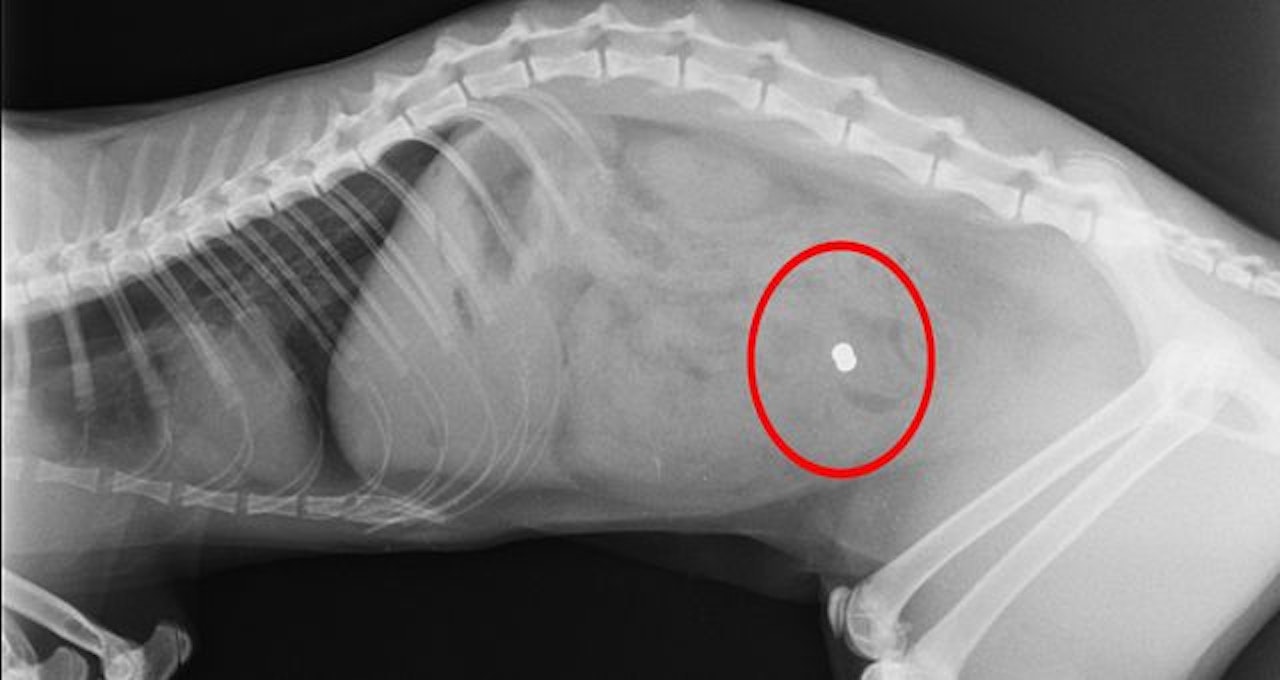

Mit Gewehr auf Katze gefeuert, Polizei ermittelt